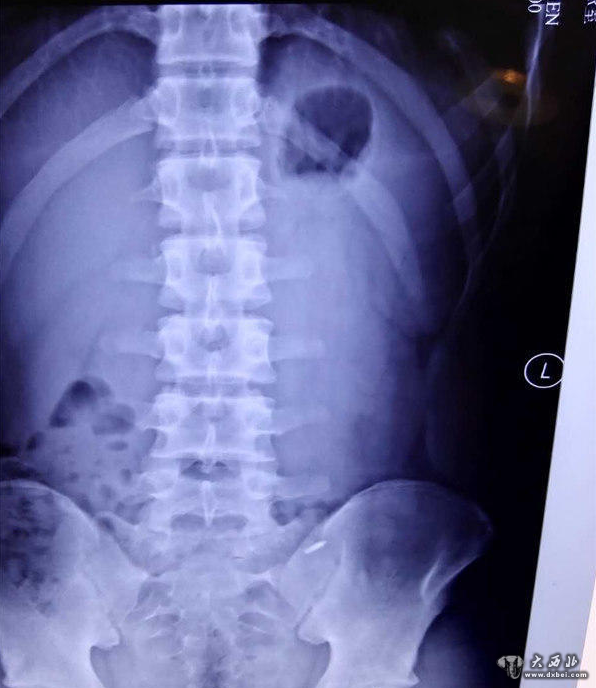

因与同学打赌,济南一名16岁的少年竟口吞一枚图钉,并将三个圆珠笔芯头从肚脐生生塞入腹腔中。事发后,少年被送至山东大学齐鲁医院急救。医生们经过4个小时的艰难寻找,才通过腹腔镜将三个圆珠笔芯头取出,而那枚图钉也在第二天被幸运地排出体外,整个过程十分惊险。

“非常难找。”李鹏宇说,王川年龄还小,为了减少创伤,他们在王川的肚脐和左右腹部各打了一个小孔,然后通过腹腔镜进行探查,但没想到在艰难地找到一个圆珠笔芯头后就再也找不到了。“由于翻找,笔芯头一直在换地方,一会在上面,一会在下面;肠子的大网膜、肠间隙非常多,情况复杂。”术中,一度医生们考虑或许只能通过创伤大的开腹手术将其取出,但考虑到孩子年龄,又坚持了下去。终于,历经了4个小时的艰难寻找,才终于把三个长1厘米左右的笔芯头给取了出来。